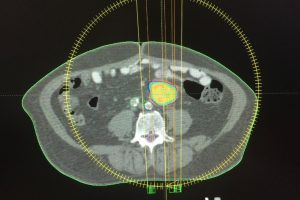

Respetando una proporción muy alta de órganos vecinos.Este proceso se lleva a cabo en varias sesiones y es un tratamiento, no una intervención quirúrgica.